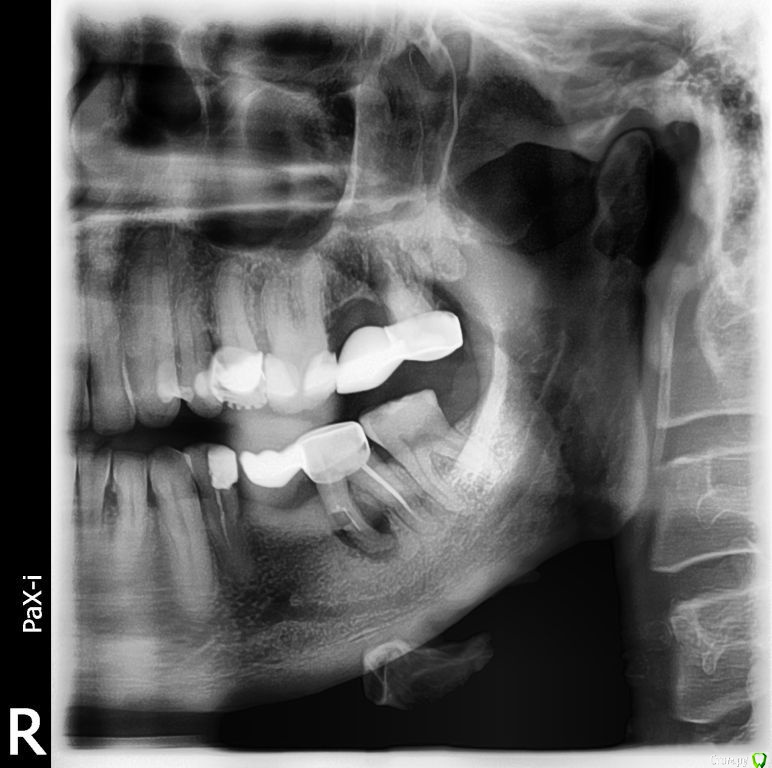

anjeys Опубликовано 10 ноября, 2018 Поделиться Опубликовано 10 ноября, 2018 Добрый день! Вот с такой радостью (на нижней челюсти) воевал я лет 10 с переменным успехом. И лечил и корни обрезал и чистил....Но чудес не бывает и после очередного пробуждения в виде свища, я с этим объектом расстался. Хирурга предупредил, что рассчитываю на имплант, кисту он вычистил, лунку не зашил. Подскажите, какую стратегию выбрать, что... когда...в какой последовательности?Противопоказаний пока не было, 50 лет. Заранее всем спасибо. Ссылка на комментарий

red_butler Опубликовано 12 ноября, 2018 Поделиться Опубликовано 12 ноября, 2018 Это уже конкретика. Спасибо. По костной ткани в зоне имплантации можно что-то сказать на сей момент? Мда...Наверное - глуповато вопрос звучит, но стирать не буду... По этому снимку можно судить только о высоте, с этим проблем нет. Ширину нужно смотреть очно и/или по Кт Ссылка на комментарий

колесников Опубликовано 12 ноября, 2018 Поделиться Опубликовано 12 ноября, 2018 У вас теперь дефект на 2 зуба. В области давней адентии явный дефицит тканей как по объёму ,так и по высоте,в области недавнего удаления -зависит от того как удаляли и как вели лунку. То что оставили открытой-не очень хорошо,будет большой дефицит тканей. Делайте клкт,далее зависит от тактики хирурга . Предположу что предложат подождать полгода ,а потом сделать костную пластику. 1 Ссылка на комментарий